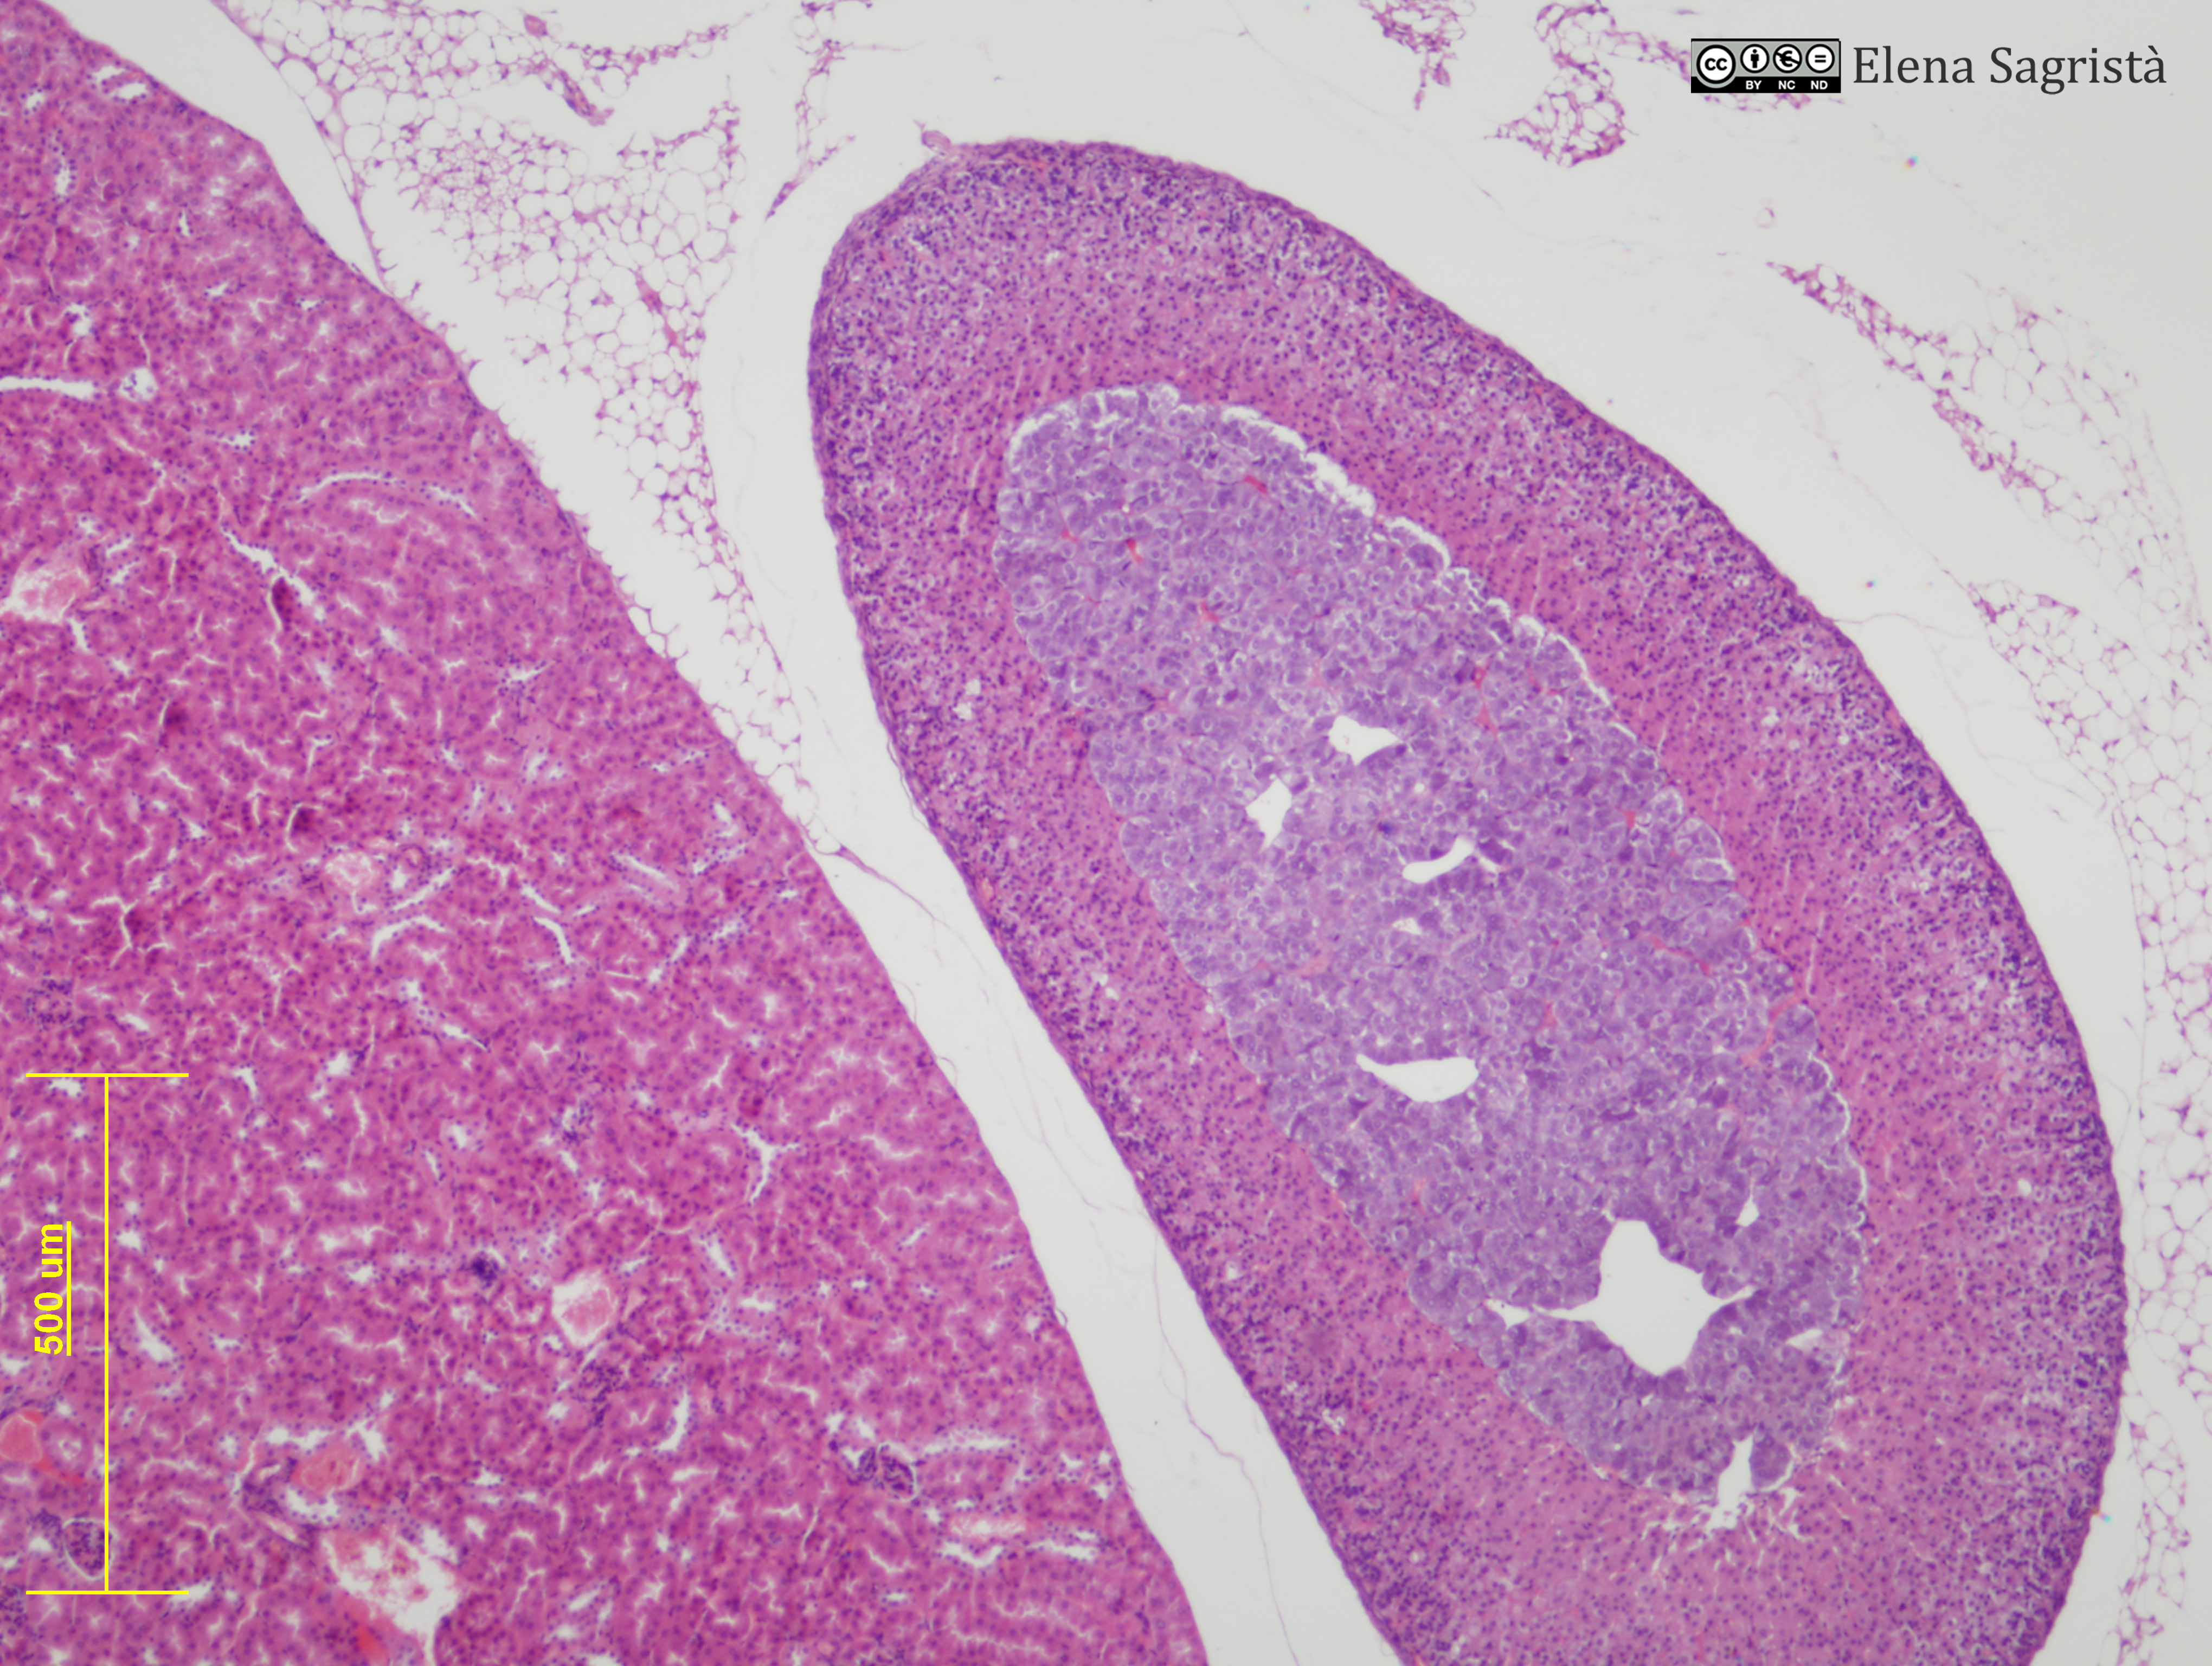

Histologia imatges: 26 Glàndula Suprarenal

Imatges de preparacions histològiques de Glàndula Suprarenal. Microscòpia òptica.

SAGRISTÀ I MATEO, Elena, Universitat de Barcelona. Departament de Biologia Cel·lular. Histologia imatges: 26 Glàndula Suprarenal. [consulta: 7 de maig de 2026]. [Disponible a: https://hdl.handle.net/2445/61486]